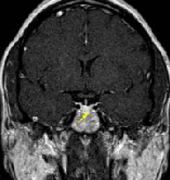

垂体瘤 作为颅内较常见的肿瘤之一,其发生率仅次于脑胶质瘤和脑膜瘤,约占颅内肿瘤的8%-15% 。尽管垂体瘤大多数为良性肿瘤,但部分患者术后已消失的...